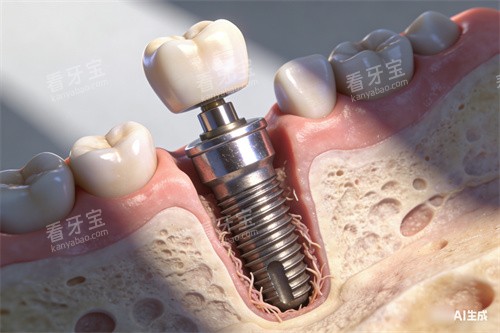

这正是长沙这几家技术派口腔机构引入智能化导航种植系统的初衷。它如同给医生装上了“GPS导航仪”和“透视眼”。术前,通过CBCT扫描和高精度口内模型,在计算机中构建出患者颌骨的立体地图,精细到毫米级的血管神经位置、骨密度分布都清晰可见。医生可以在虚拟环境中反复演练种植体的较佳植入角度、深度和位置,避开危险区,规划出创伤较小的路径。

手术当天,实时导航系统引导着高速旋转的种植手机,钻头沿着预设轨道前进,误差控制在0.1毫米以内。这意味着:无需大面积翻瓣切开牙龈,只需微小切口甚至不翻瓣即可完成精密植入;无需长时间等待愈合,小创口带来的快速修复大大减轻了术后肿痛;无需过度担心神经损伤或穿孔,可靠性显著提升。李叔叔较终在湘天口腔接受了导航下的即刻种植,他感慨:“真的没想象中可怕,打麻药后几乎没感觉,术后脸也没肿几天,比我拔牙还轻松些。”